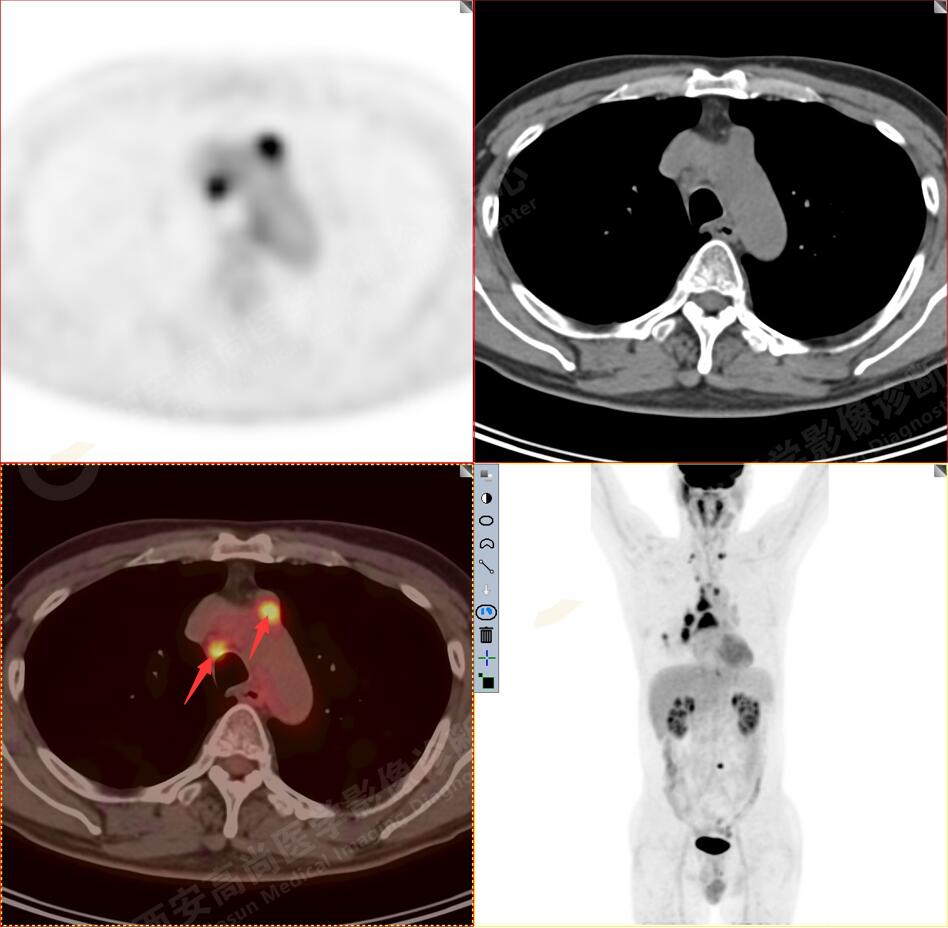

1.以下為肺內(nèi)原發(fā)灶

1.右肺下葉后基底段軟組織結(jié)節(jié)(約1.5cm×1.2cm),與相鄰后胸膜分界不清,呈FDG代謝異常增高,結(jié)合病理,符合肺腺癌伴鄰近胸膜侵犯。